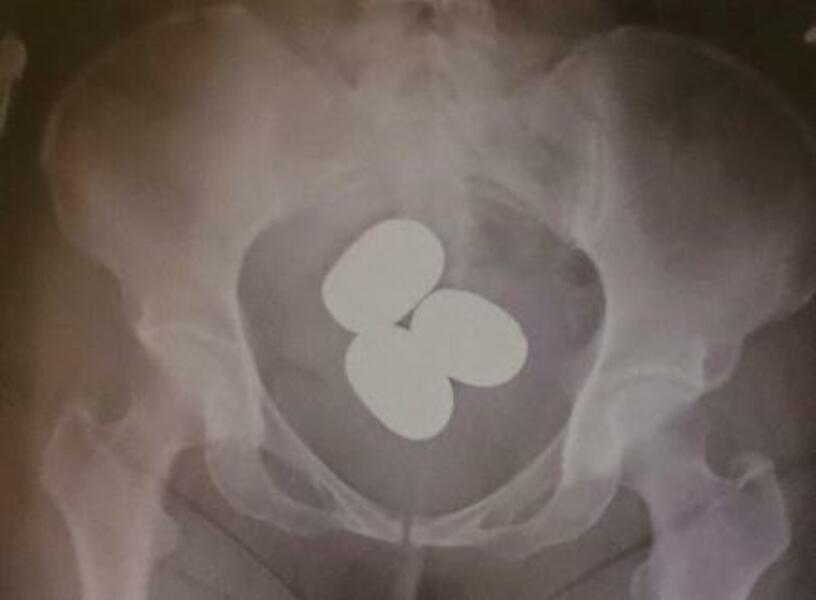

東京税関成田税関支署が公表した、香港からの旅客が体内に粉状の金を隠し密輸しようとした摘発事例(同署提供)